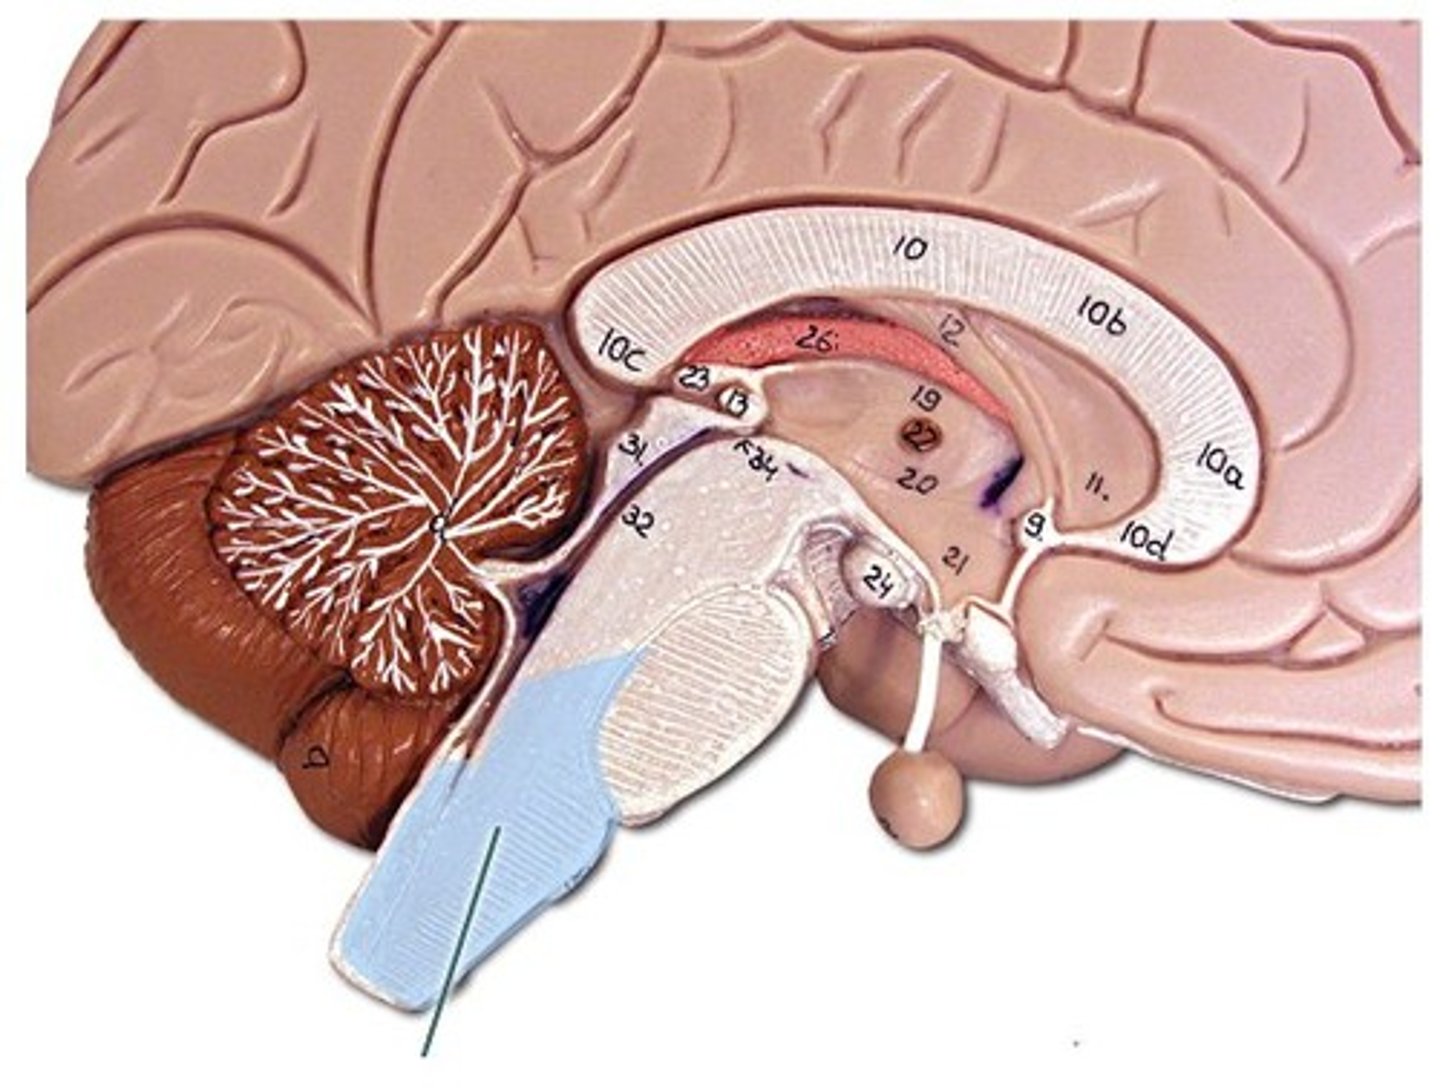

Corpus Callosum

Fibers connecting both halves of the brain, c shaped structure

Fornix

fiber tract linking limbic system regions

Diencephalon

made up of epithalamus, thalamus and hypothalamus

Hypothalamus

forms floor of 3rd ventricle , cap over brain dtem and 3rd ventricle. Visceral control center, 3 fs

Infundibulum

the hollow stalk that connects the hypothalamus and the posterior pituitary gland.

Pituitary Gland

the major endocrine gland. A pea-sized body attached to the base of the brain, the pituitary is important in controlling growth and development and the functioning of the other endocrine glands.

Cerebellum

"little brain" attach to the top of the brain stem. Components include vermis, arbor vitale, cortex, peduncles

Brain Stem

Continuation of spinal cord. Contains medulla oblongata, pons and midbrain

Pons

bulging brain stem region between midbrain and medulla.

Medulla Oblongata

most inferior part of brain stem, eventually becomes spinal cord. Autonomic reflex center.